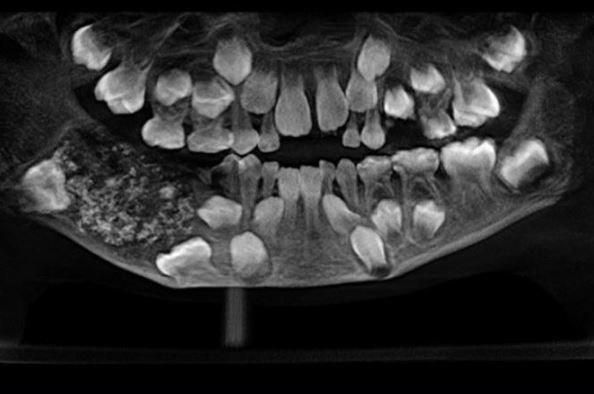

Doctors at the Saveetha Dental College and Hospital in India were surprised to find that a 7-year-old boy brought to their outfit was actually having 526 extra teeth in his mouth.

Reports say the youngster was admitted in July because of swelling and pain near his molars in his lower right jaw.

A team of doctors at the Oral and Maxillofacial Pathology headed by Dr. Prathiba Ramani conducted a scan and spotted a sac embedded in his lower jaw filled with “abnormal teeth.”

It took the team of doctors four to five hours to empty the sac, only to realise that it contained 526 teeth.

“There were a total of 526 teeth ranging from 0.1 millimeters (.004 inches) to 15 millimeters (0.6 inches). Even the smallest piece had a crown, root and enamel coat indicating it was a tooth,” Dr. Prathiba Ramani is quoted as saying.

She explained that the boy was suffering a very rare condition called compound composite odontoma whose cause is not yet known.